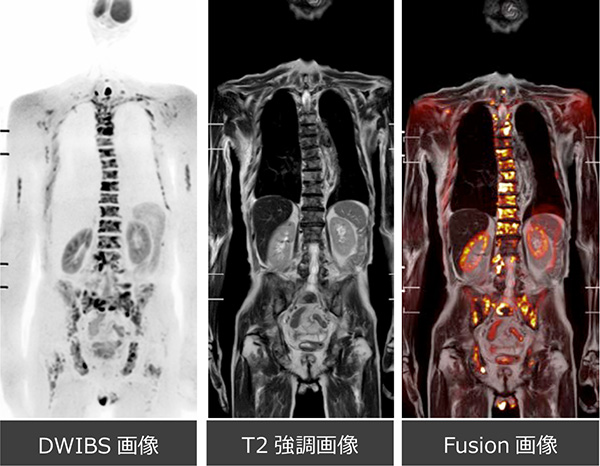

MRI(DWIBS)の推奨

精確な治療を行うために、がんの検出と治療評価に役立つ先端のMRI技術であるDWIBSによる画像診断を推奨しています。

DWIBSは放射線を使用しないため、繰り返しの検査にも適しており、非侵襲的にがん細胞の位置や状態を高精度で捉えることができます。

この技術は、多くの種類のがん、特に複雑な場所に存在するがんに対しても有効であり、治療計画の策定や治療効果の確認に貢献しています。

DWIBSを利用することでがんの勢いを詳細に把握できるため、治療箇所の優先順位を特定し、治療の精度を向上させることが可能です。